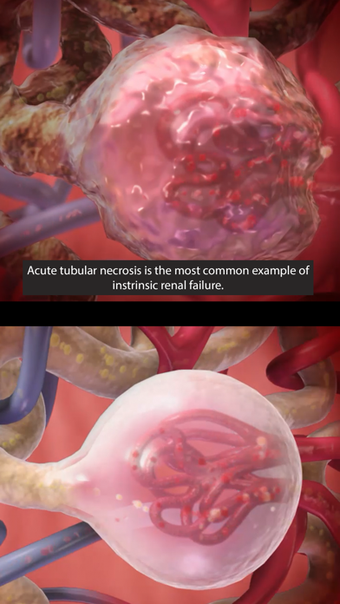

Argosy Publishing による iPhone 用の完全版アプリ。

Physiology Pathologyは iPhone 用のフル バージョンのソフトウェアで、 「医学」カテゴリの一部です。

iPhone用の生理学病理学について

生理学 病理学は、iOS 12.1.2 以降で利用できます。アプリの現在のバージョンは 1.1.39 で、英語、ドイツ語、イタリア語で実行できます。